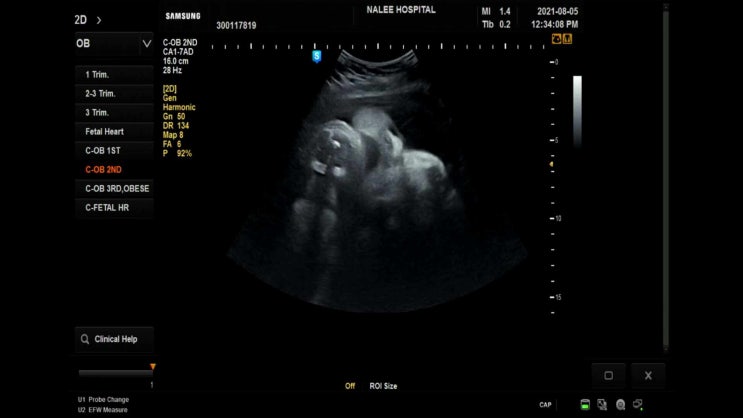

20210805 38주차 출산전 마지막 병원 검진

어느덧 다음주면 출산 예정일 아직까지 나오려는 느낌도 변화도 없다 일주일간 열심히 걸었어야 했나보다 ...